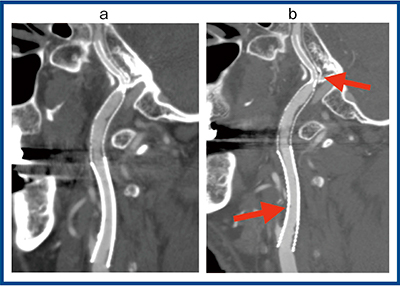

頸部血管領域においても,Aquilion Precisionの超高精細画像によって石灰化やステント内腔の描出能が向上し,より正確な評価が可能になった。図6は,右内頸動脈狭窄症に対してステント治療が繰り返され,縦長に複数のステントが留置されている。ADCT(a)では,上部のステント内が狭窄していると思われる部分は,パーシャルボリュームエフェクトとブルーミングアーチファクトの影響で内腔が潰れて評価できない。Aquilion Precision(b)では,内腔の評価が可能で(→),ステント直下のプラークも確認できる(←)。

図6 右内頸動脈狭窄ステント留置症例の比較画像

a:ADCT b:Aquilion Precision